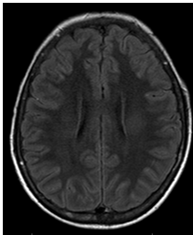

A CT (Computerized Tomography) scan of the skull was requested and did not show any signs of intracranial hemorrhage. Subsequently, magnetic resonance imaging (MRI) of the brain was performed, evidencing two focal areas of high signal in DWI in bilateral centrum semiovale (Figures 1‒5). Considering that the treatment wasn`t finished and still consisted in high and continuous doses of MTX, aminophylline was introduced in order to prevent/reverse the effects of the subacute ischemic event due to the medication.

Figure 2 FLAIR images showing no abnormalities.

Figure 3 FLAIR images showing no abnormalities.